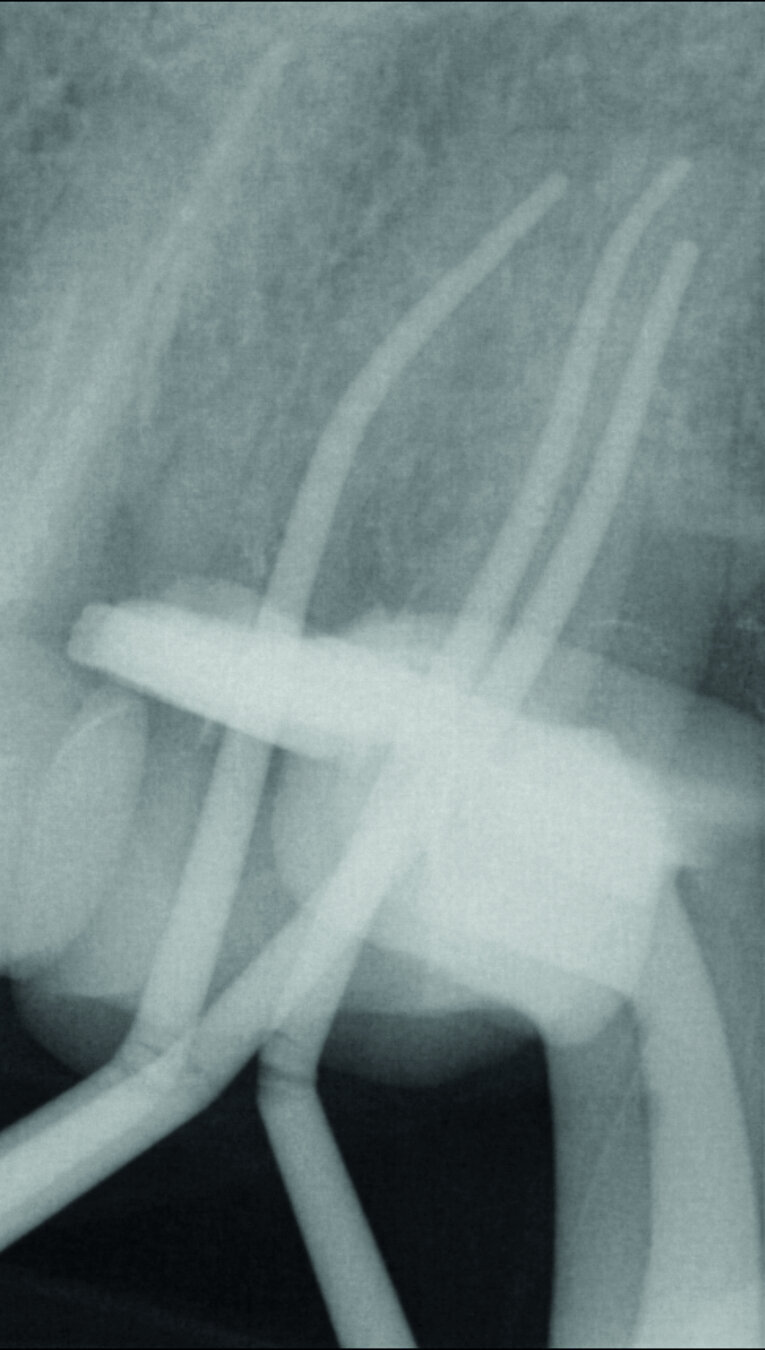

À gauche : Maîtres cônes mis en place dans le canal ; à droite : Radiographie des maîtres cônes pour confirmer la longueur de travail définie. (Photos : Dr Georg Benjamin)

Fig. 5 : Radiographie de la fermeture de la perforation après la première visite.

Fig. 10 : Radiographie des maîtres cônes pour confirmer la longueur de travail définie.

Le matériau d’obturation du canal radiculaire (Figs. 9 et 10) a été enfoui aussi profondément que possible afin de parvenir à une surface de rétention adhésive maximale pour la fermeture post-endodontique, puis un sablage par Al2O3 a été réalisé (Fig. 11). Ensuite, everX Flow de teinte translucide (Bulk) a été utilisé et a comblé un hiatus dans mon protocole de traitement. Le produit s’écoule très bien, sans formation de bulles, dans la profondeur des canaux et il permet donc l’obturation des petits canaux radiculaires avec un matériau composite renforcé en fibres de verre (glass fibre reinforced material, FRC). Dans ce cas, j’ai utilisé everX Posterior, de viscosite plus élevée, selon la technique dite de chasse-neige.